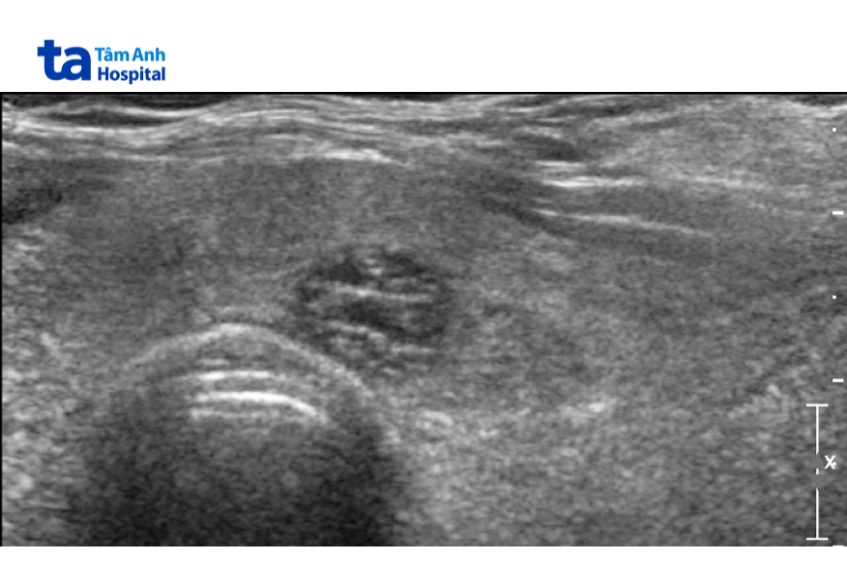

Nhân bọt biển tuyến giáp là dạng khối u bất thường tại tuyến giáp. Nhân này có ít nhất 50% thành phần là các nang nhỏ, hình ảnh trên siêu âm tương tự như miếng bọt biển.

Nhân bọt biển được mô tả trên siêu âm với các đặc tính:

Giống như phần lớn các nhân giáp, nhân giáp dạng bọt biển thường lành tính. Theo phân loại TIRADS (Thyroid Imaging Reporting and Data System – hệ thống phân loại nguy cơ ác tính của nhân tuyến giáp trên siêu âm), bệnh được xếp vào nhóm TIRADS 1 – 2, chỉ cần theo dõi định kỳ, không cần chọc hút bằng kim nhỏ (FNA) nếu kích thước < 2,5cm. (2)